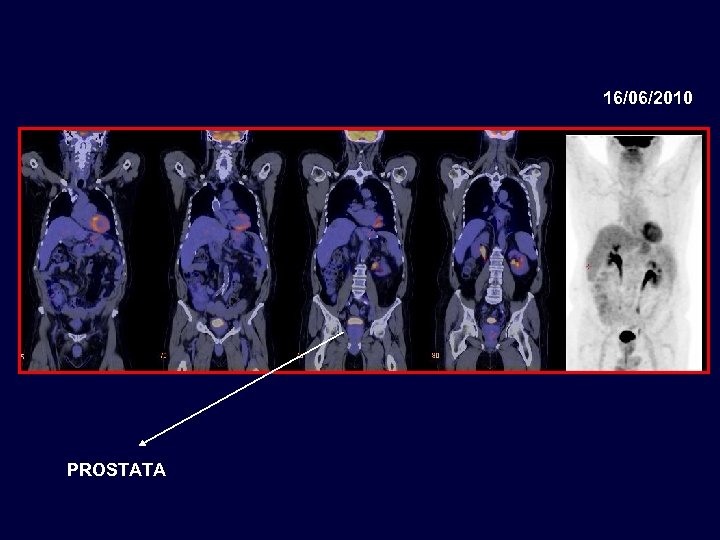

16/06/2010 PROSTATA